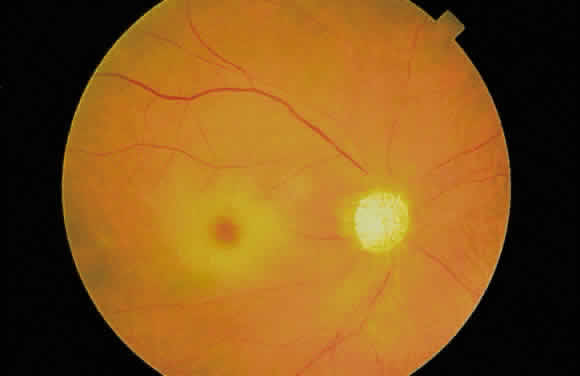

Fig. 27. Fundus photographs of quiescent toxoplasmosis chorioretinitis scar. The

white center is the result of destruction of the neurosensory retina, retinal

pigment epithelium, and choroid, leaving only the sclera in view. Fig. 27. Fundus photographs of quiescent toxoplasmosis chorioretinitis scar. The

white center is the result of destruction of the neurosensory retina, retinal

pigment epithelium, and choroid, leaving only the sclera in view.